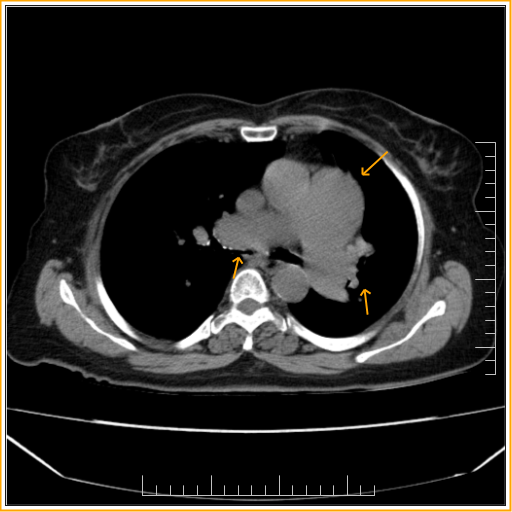

Long standing left to right shunt-CT

- Cardiomegaly

- Dilatation of the main pulmonary artery along with dilatation of bilateral central pulmonary arteries. These findings are suggestive of possible PAH possibly secondary to long standing left to right shunt. Requires echocardiographic evaluation.

- Atherosclerotic calcification involving the aortic arch and vessels.